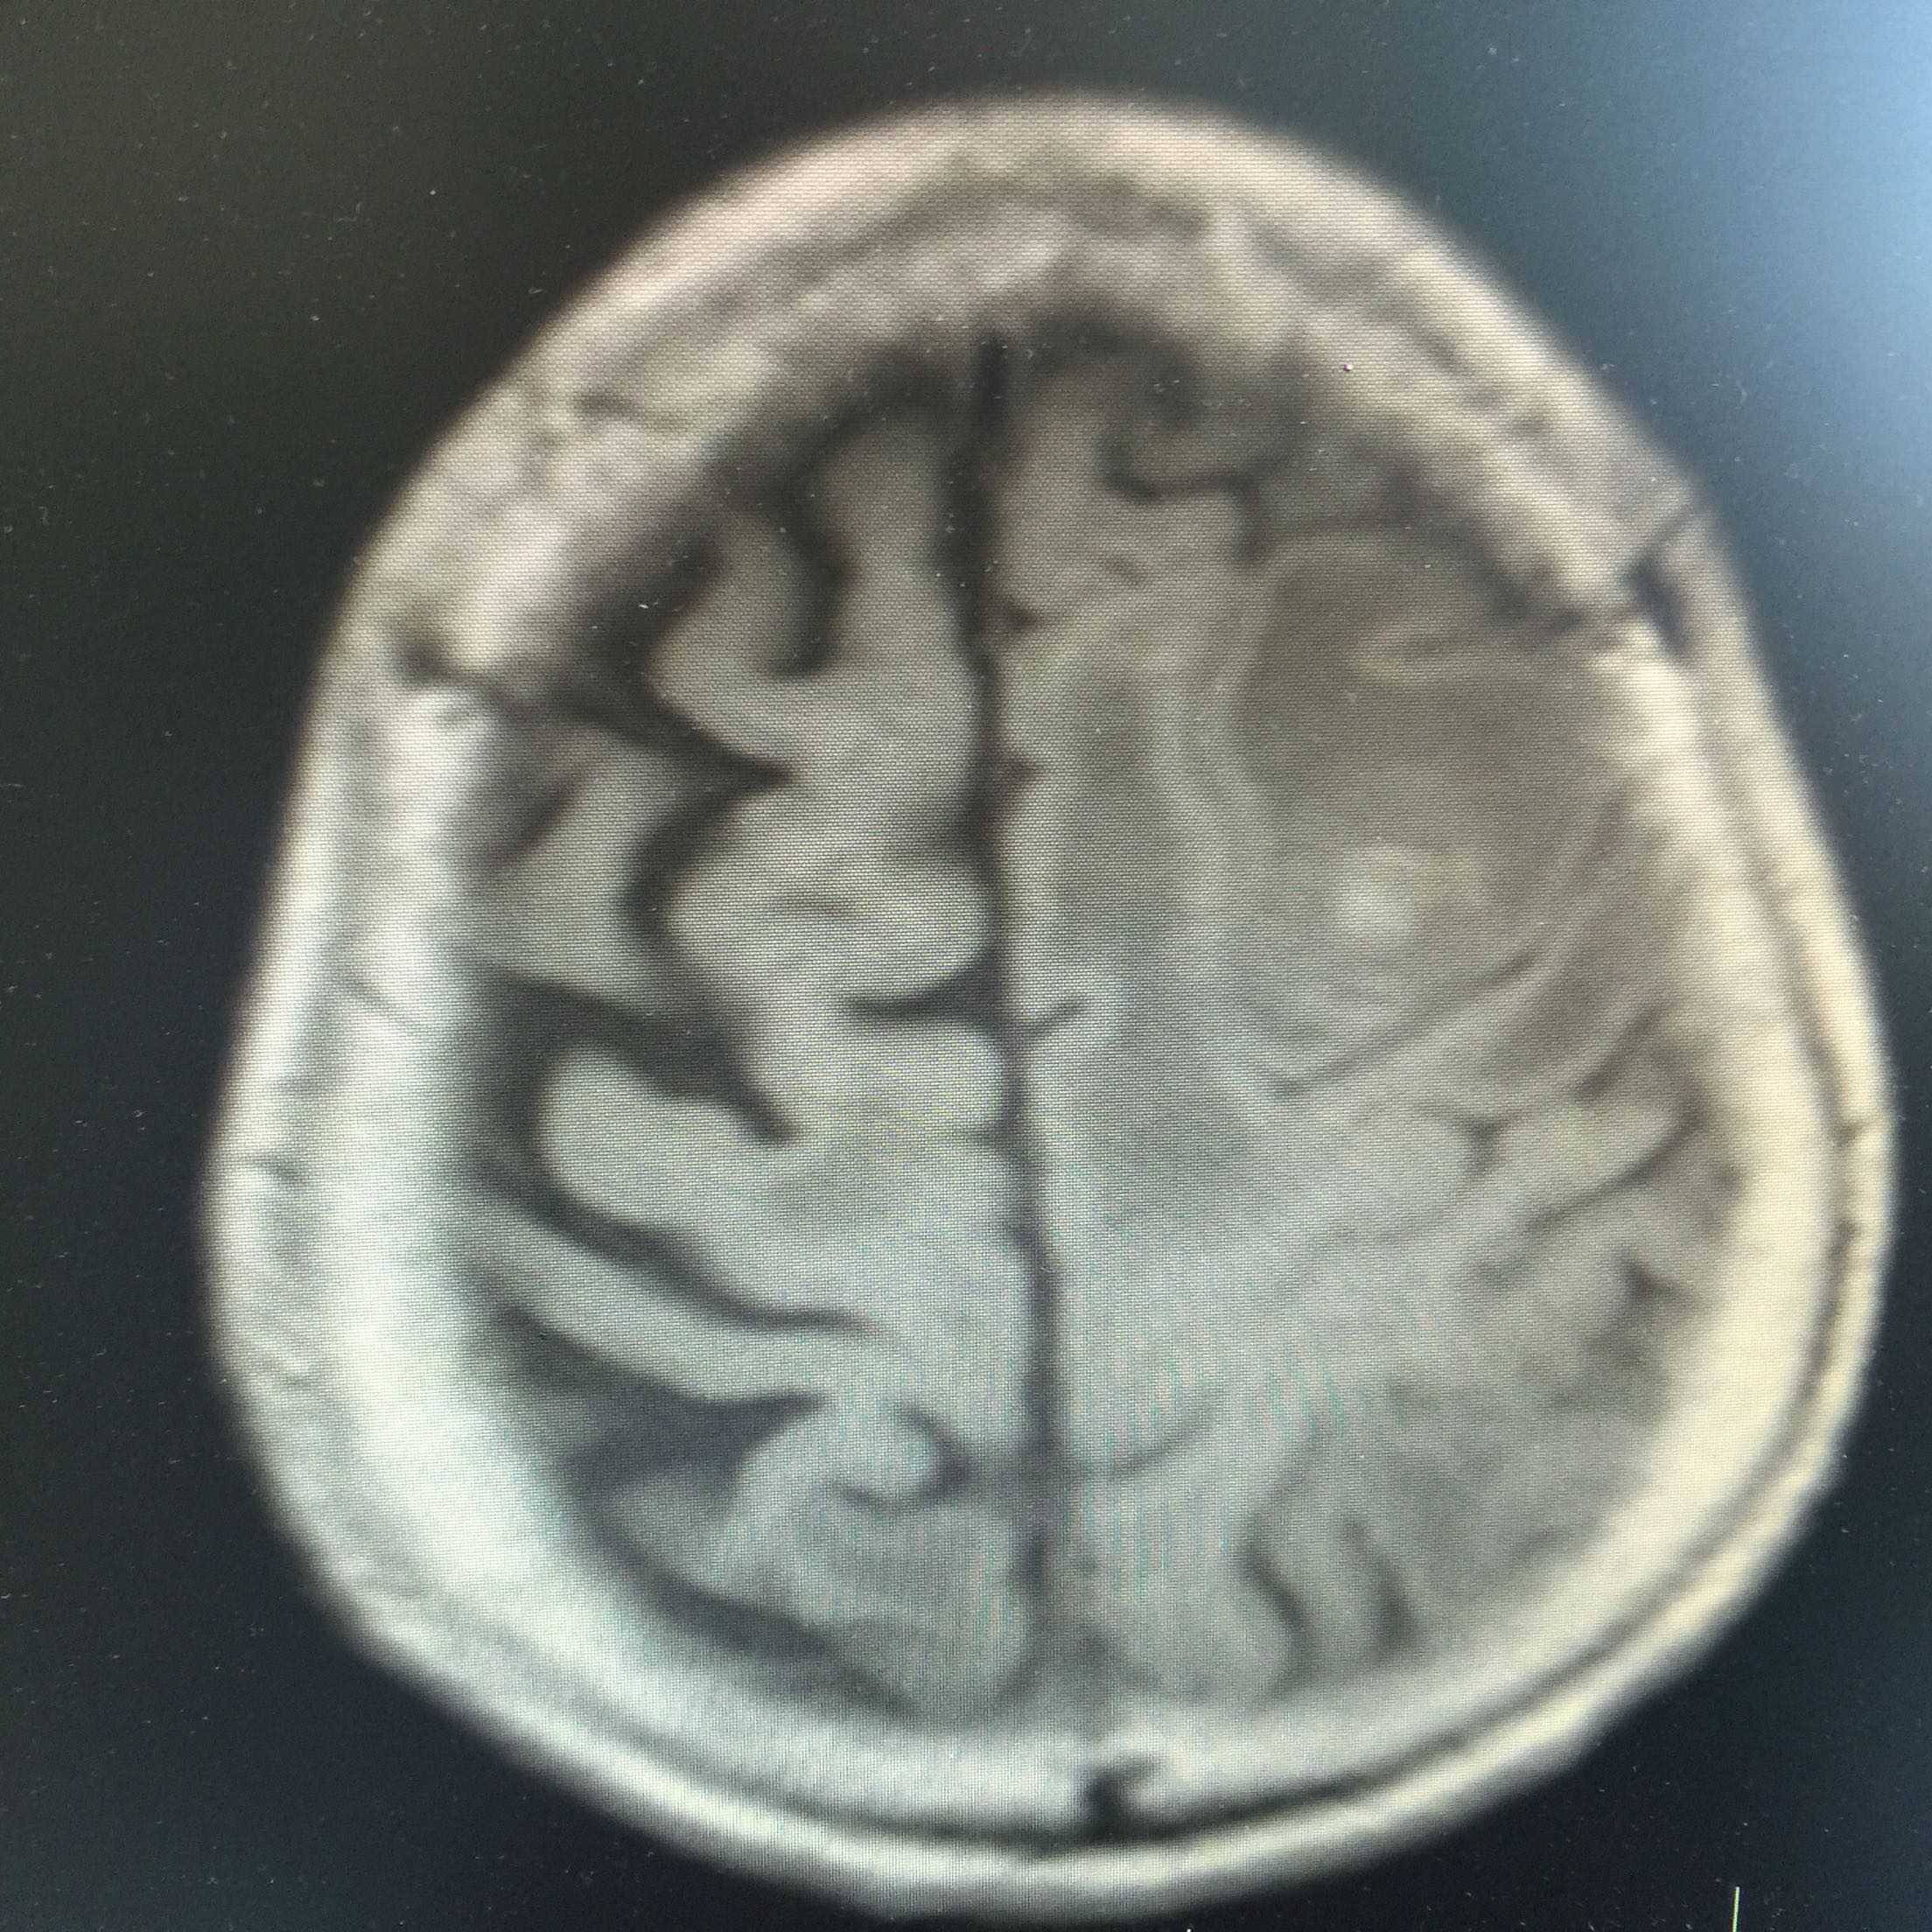

1.女,81岁,以“右侧肢体无力3天”入院。 2.现病史:3天前无诱因出现右侧肢体无力,右上肢抬举费力,右下肢步行拖拉,无抽搐,无意识障碍! 3.既往史:2016年肺穿刺活检,免疫组化为腺癌!已合并第五、六椎体转移、左肾上腺转移,行灌注介入治疗。

查体:血压:130/80mmHg,两肺呼吸音清,未闻及啰音,心率98次/分,律齐,未及杂音,双下肢无水肿。神经系统查体:意识清,双侧瞳孔等大正圆,直径约3.0mm,对光反射灵敏,无面舌瘫,右侧肢体肌力4级,腱反射减弱,Babinski征R+L-。

左肺腺癌 骨转移、双肺门及纵膈淋巴结转移、左肾上腺转移、脑转移! 治疗:对称、支持治疗!